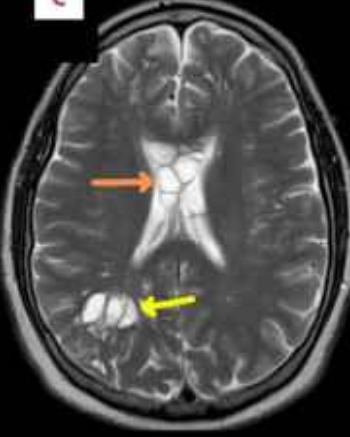

Un caz medical ieșit din comun a stârnit îngrijorare în rândul medicilor: un bărbat de 52 de ani s-a prezentat la spital după ce migrenele sale obișnuite au devenit greu de controlat, iar tratamentele uzuale nu-l mai ajutau. Investigațiile imagistice au dezvăluit prezența ouălor de tenie la nivel cerebral, un tablou compatibil cu cisticercoza – o afecțiune cauzată de pătrunderea și dezvoltarea larvelor de tenie în țesuturi.

Potrivit medicilor, schimbarea bruscă a intensității durerilor de cap a determinat efectuarea unor teste avansate. Tomografiile cerebrale au scos la iveală leziuni cu aspect caracteristic infestării parazitare. În termeni simpli, organismul bărbatului a fost invadat de forme imature de parazit, localizate în creier, fapt ce explică persistența și agravarea simptomelor.

Durerea de cap – în special atunci când se modifică brusc prin intensitate sau frecvență – este un semnal de alarmă ce trebuie investigat. În acest caz, tocmai agravarea simptomelor a dus la realizarea unor imagini detaliate ale creierului, care au clarificat diagnosticul. Identificarea rapidă a cauzei a permis conturarea unui plan medical adecvat, în funcție de localizarea și numărul leziunilor observate.

Pacientul a ajuns la spital după ce migrenele nu au mai răspuns la medicația obișnuită, iar investigațiile imagistice – inclusiv tomografia cerebrală – au indicat prezența ouălor de tenie în creier, compatibile cu cisticercoza.